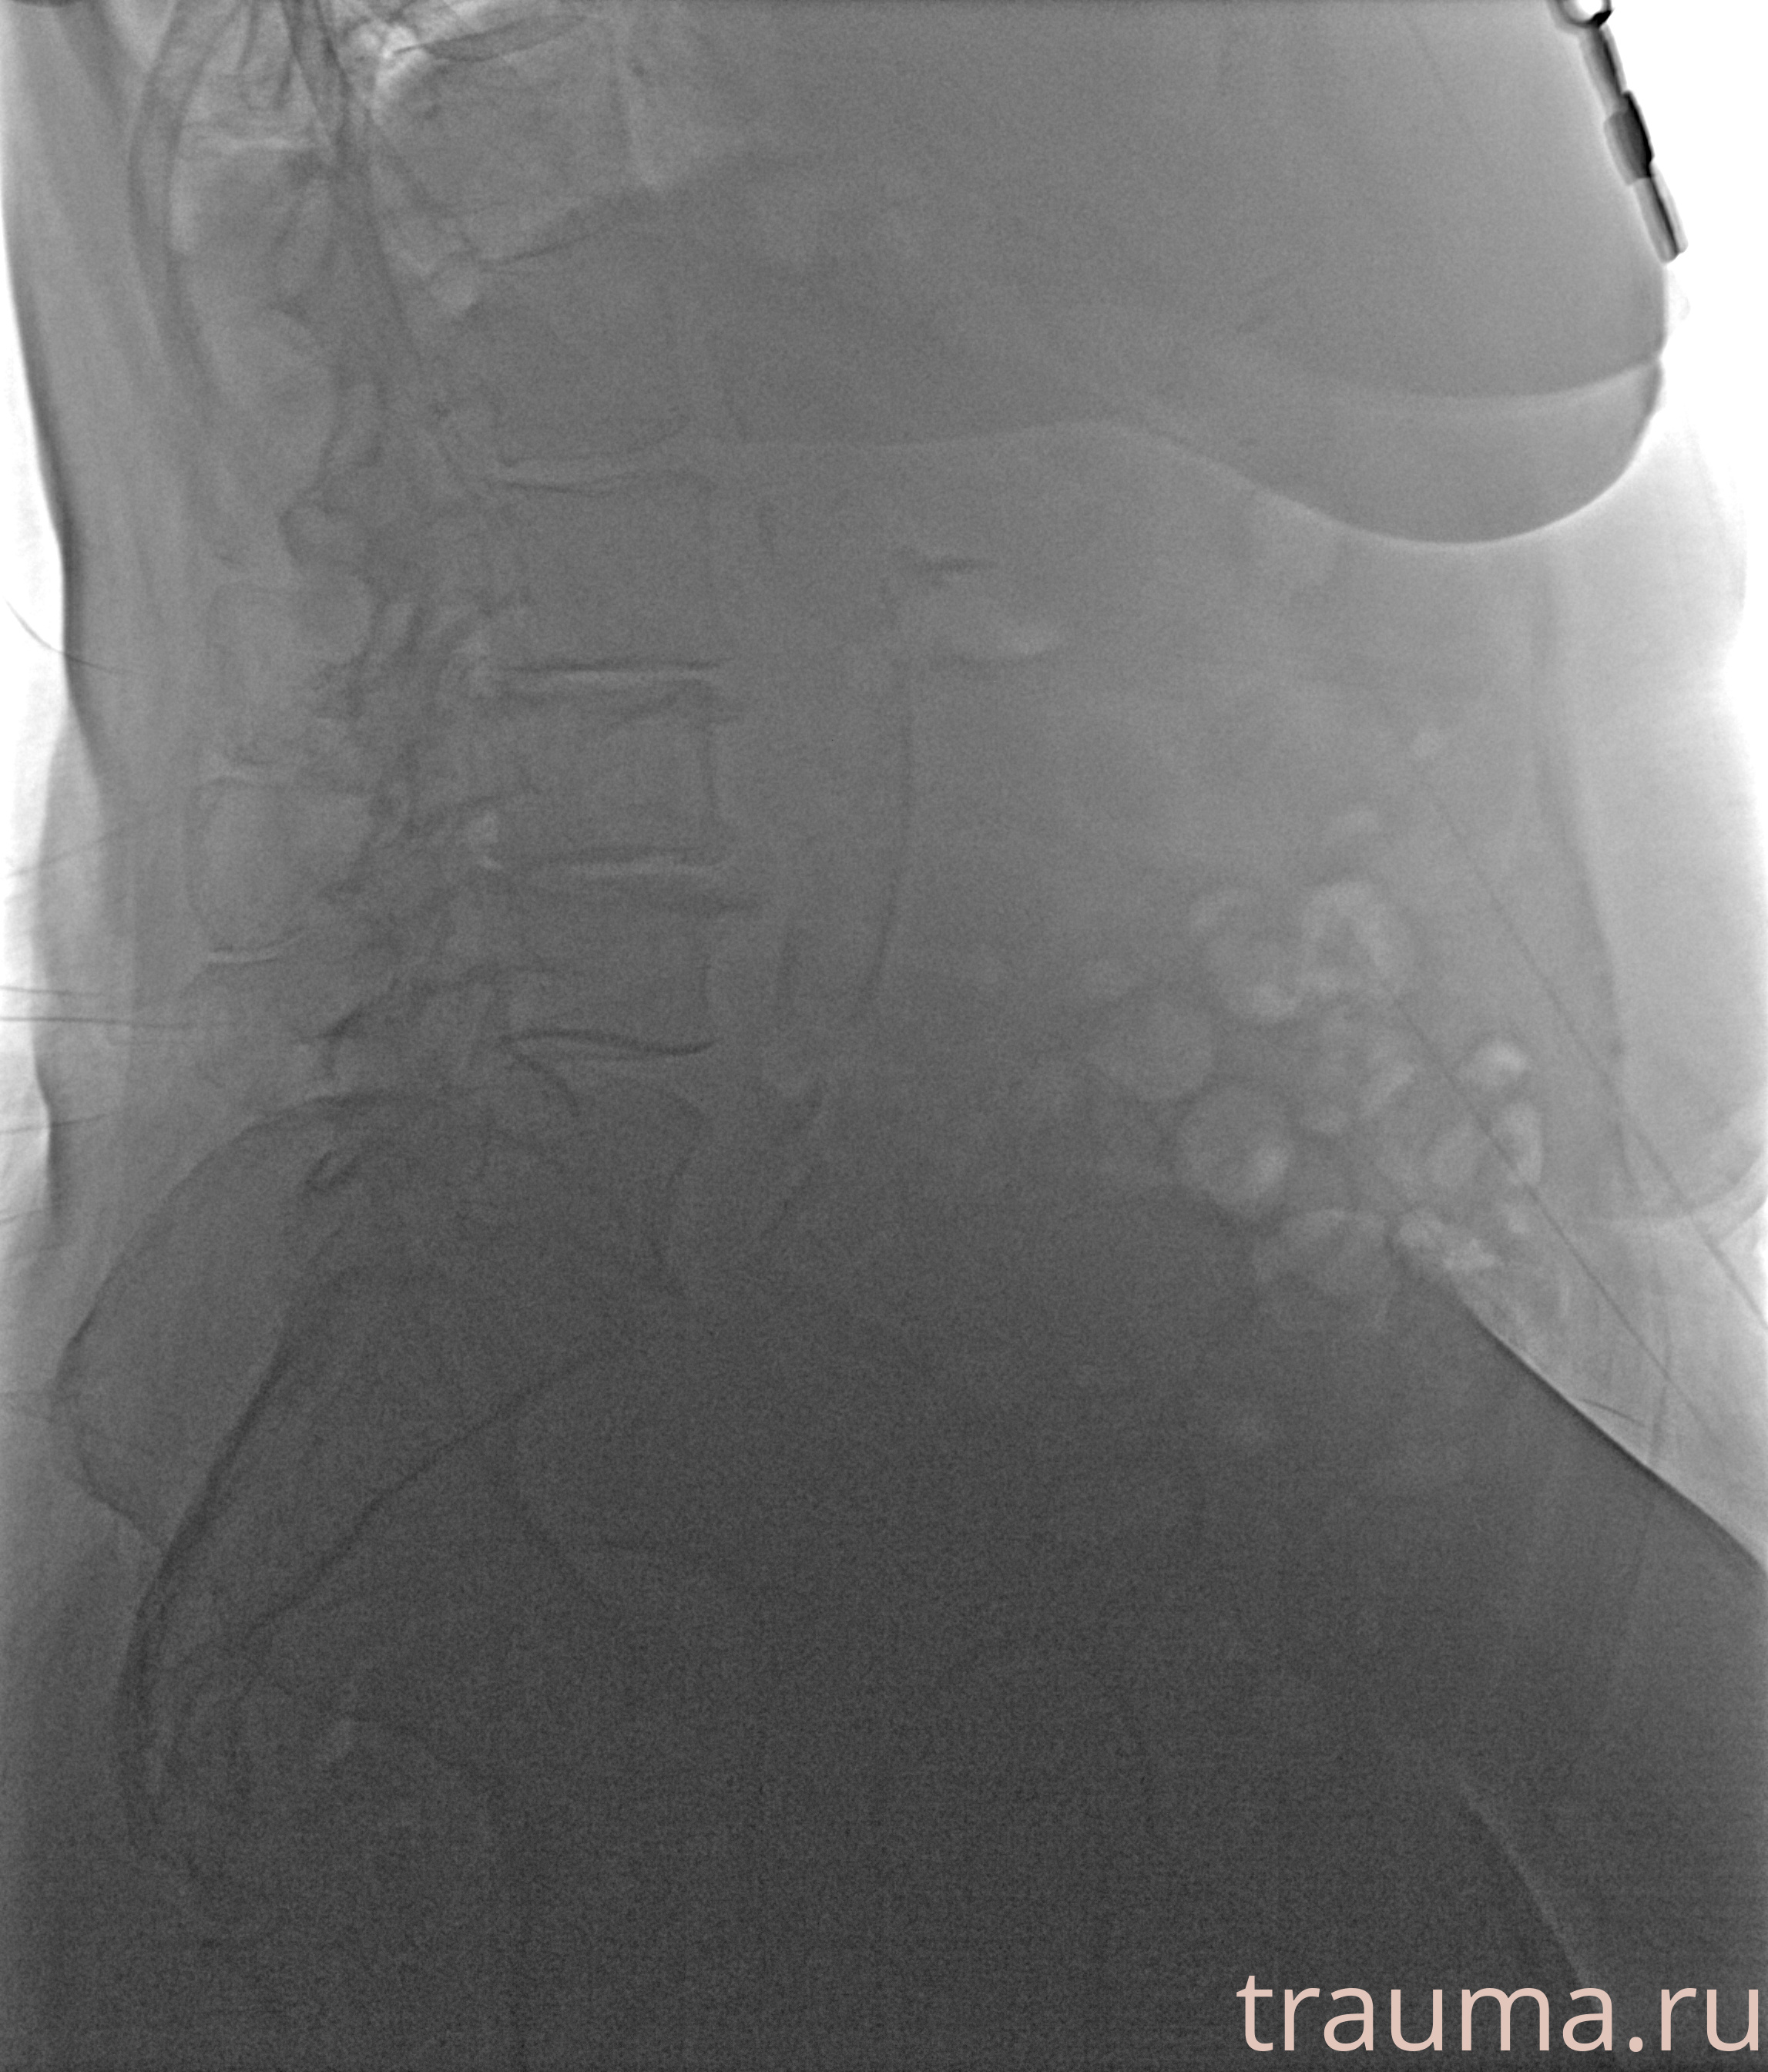

Рентген на дому: по вашему адресу приезжает врач-рентгенолог, травматолог-ортопед с мобильным рентгеновским аппаратом, проводит диагностику травмы или заболевания, делает необходимые рентгенограммы, дает рекомендации по дальнейшему лечению. Получить качественные снимки в домашних условиях возможно благодаря уникальной методике, разработанной МосРентген Центром для института  Склифосовского

при переломе шейки бедра и пневмонии от компании МосРентген Центр - партнера Института имени Склифосовского